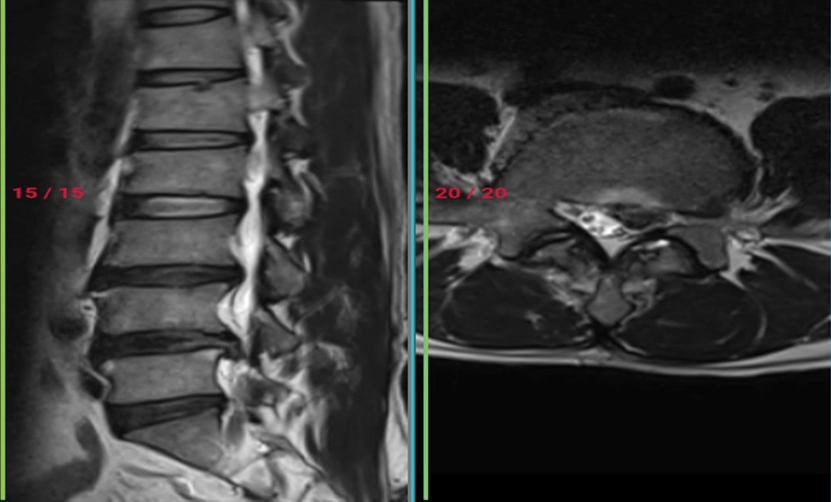

− Chụp cộng hưởng từ cột sống: chỉ định trong trường hợp có thoát vị đĩa đệm.

Điều trị Phục hồi chức năng kết hợp cho bệnh nhân tại Bệnh viện Đa Khoa Tỉnh Quảng TrịĐiều trị bằng Phương Pháp Y học cổ truyền: Xông hơi thuốc, điện châm, xoa bóp bấm huyệt…. tại bệnh viện Đa khoa Tỉnh Quảng TrịMRI của Bệnh nhân thoát vị đĩa đệm - hẹp ống sống, được điều trị bằng phương pháp

Phẫu thuật tại bệnh viện đa khoa tỉnh Quảng Trị